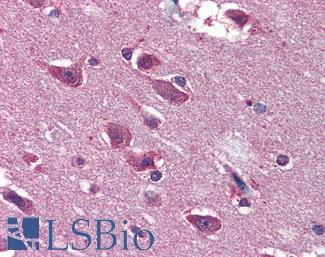

SATB2

Anti-SATB2 antibody IHC of human brain, cortex. Immunohistochemistry of formalin-fixed, paraffin-embedded tissue after heat-induced antigen retrieval. Antibody LS-B4981 concentration 5 ug/ml.